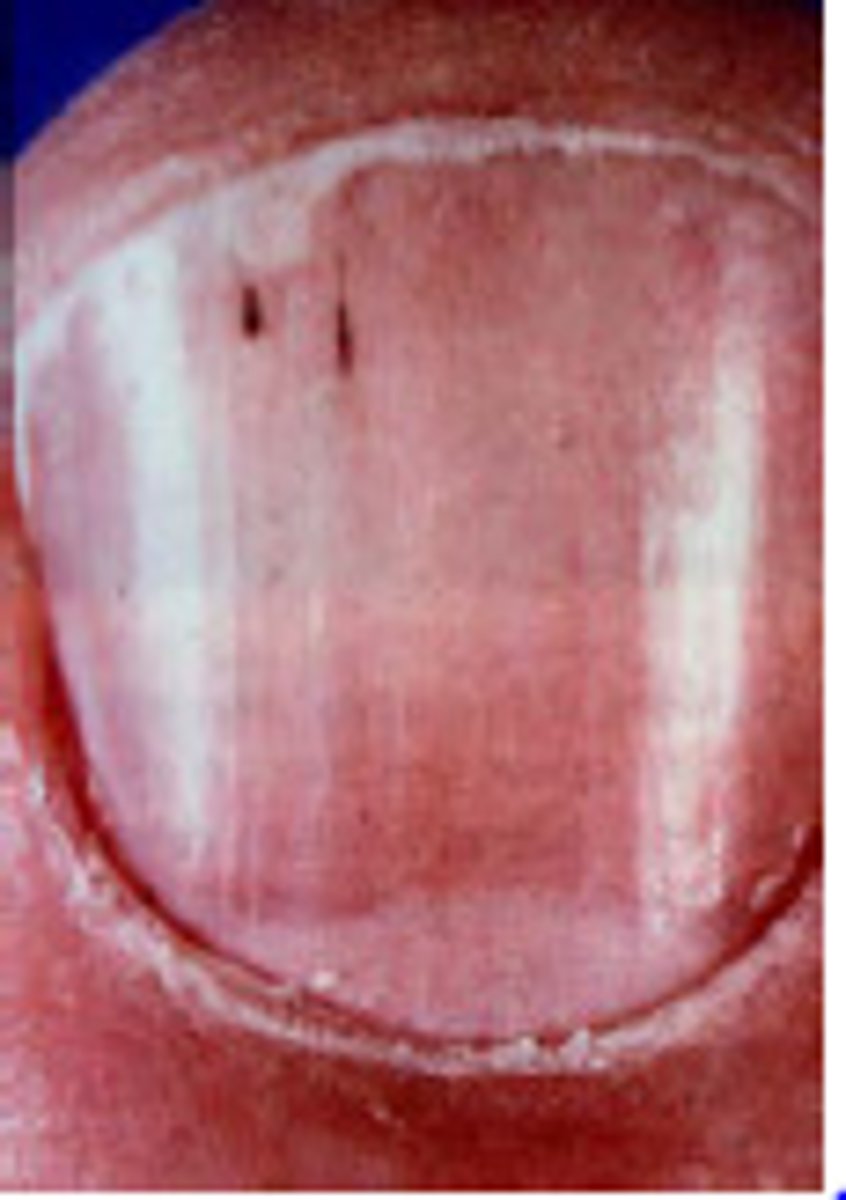

Splinter hemorrhages in fingernails

Bacterial endocarditis